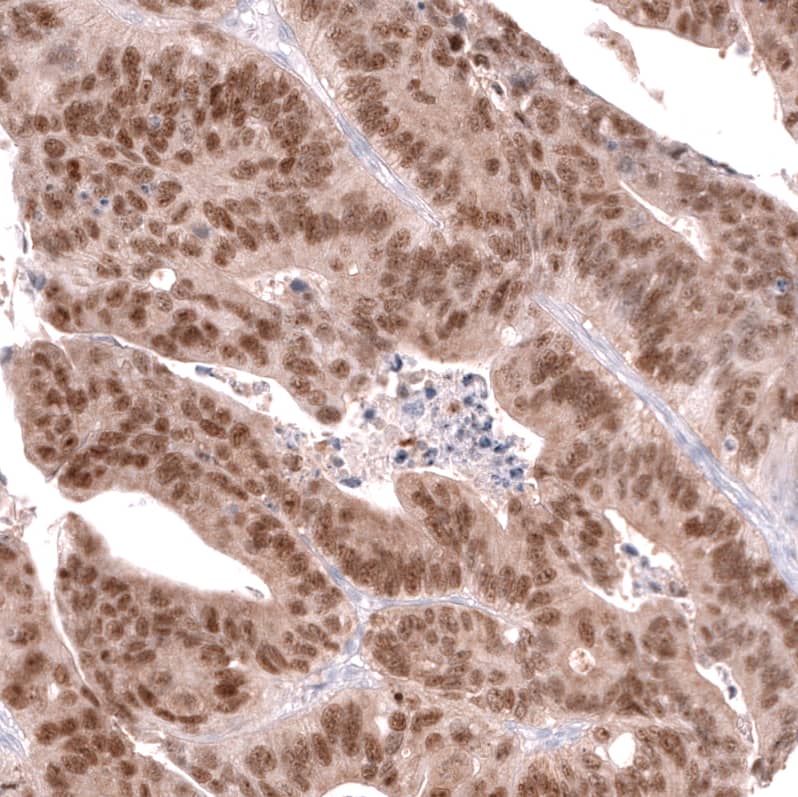

Staining of human colorectal cancer (metastasis to ovary) shows moderate to strong nuclear positivity in tumor cells.

Staining of human colorectal cancer shows strong nuclear positivity in tumor cells.